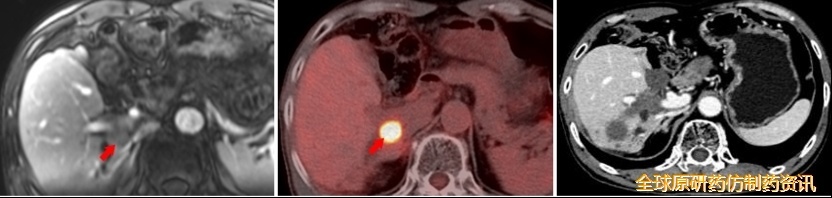

靶免联合方案治疗3个月后复查(2021.12)

AFP 8731 ng/mL;

MRI示肝S9c段下方稍低信号结节;

PET/CT提示S9c段结节氟代脱氧葡萄糖(FDG)代谢明显增高;考虑S9c段复发;全身其他部位糖代谢未见明显异常。

予以靶免联合方案+SBRT治疗(2022.01.06)

在“双艾”方案基础上对Ⅸc段复发病灶行SBRT治疗(共7次,累计剂量为56Gy);

放疗后,继续使用“双艾”方案治疗。

靶免联合方案+SBRT治疗后2个月后复查(2022.03)

AFP 2.91 ng/mL;

CT示肝Ⅸc段未见强化影,疗效评价为完全缓解(CR)。

图14 复发转移及治疗复查结果对比